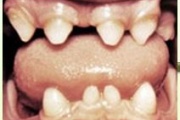

Puudub ülemine tsentraalne intsisiiv, kuid külgmised lõikehambad on juba lõikunud.

Turritavad ülemised lõikehambad.

Puudub ülemine tsentraalne intsisiiv